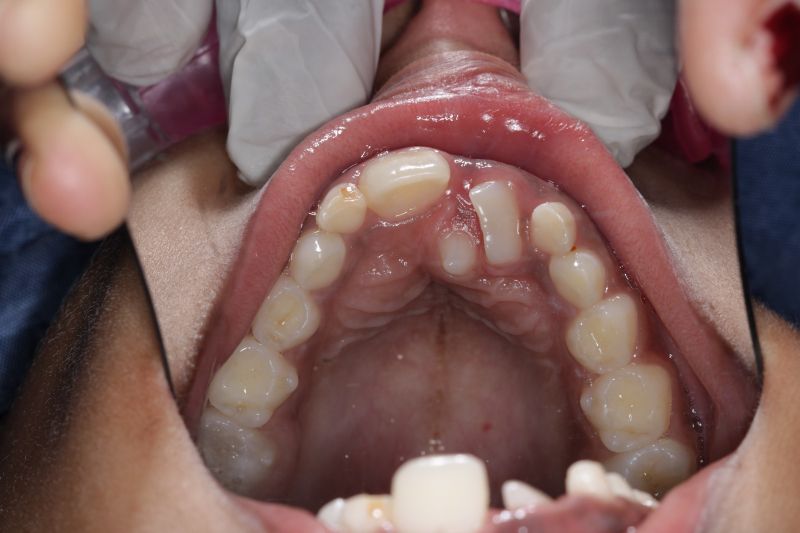

Early braces treatment correct the irregularly placed teeth and create room for erupting permanent teeth. correct bite problems such as open bite, cross bite and improves the appearance and self esteem of the child.